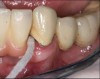

The first step in preventive strategies must be to perform a correct diagnosis of the peri-implant condition by accurately assessing the health of the peri-implant hard and soft tissues through periodontal probing and periapical radiographs at the time of definitive prosthetic installation. These measurements should be considered the baseline diagnosis and, therefore, represent a true starting point for evaluating the changes on the radiographic bone levels and probing pocket depths (PPD) at future recall appointments (Figure 1 and Figure 2).6 Although probing depth measurements of peri-implant tissues do not have the same diagnostic value as probing periodontal tissues, there is evidence that BOP is the most objective sign of peri-implant tissue inflammation; significant deepening of PPD compared with baseline measurements is also a sign of disease that indicates the need to perform a radiographic evaluation (Figure 3 through Figure 5).6,10,11

Fig 3. Peri-implant mucositis: mucosal inflammation.

Figure 3

Fig 4. Bleeding on probing.

Figure 4

Fig 5. Radiograph showing no bone loss.

Figure 5